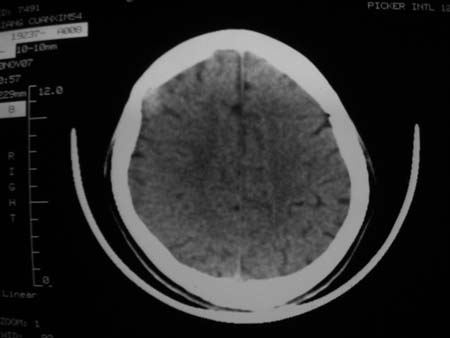

男,54岁,十天前被钢管打伤头顶部,现自述头部不适,视物模糊,并于两天前发觉右枕部有包块,既往未有明显异常.

颅骨多处骨质不完整,内板变薄,右侧额颞部局部呈“穿凿样”骨质缺损,相应区硬膜外密度略增高。多考虑:骨嗜酸性肉芽肿!

颅骨多处骨质不完整,内板变薄,右侧额颞部局部呈“穿凿样”骨质缺损,相应区硬膜外密度略增高。多考虑:骨髓瘤或骨嗜酸性肉芽肿!

颅骨多处骨质不完整,内板变薄,右侧额颞部局部呈“穿凿样”骨质缺损,缺损骨质边缘锐利无硬化,相应区硬膜外密度略增高。多考虑:骨嗜酸性肉芽肿!

颅骨多处骨质不完整,内板变薄,右侧额颞部局部呈“穿凿样”骨质缺损,相应区硬膜外密度略增高。多考虑:骨髓瘤或骨嗜酸性肉芽肿!10天前受伤,不会在2天前才发现头部包块,估计与外伤无关.